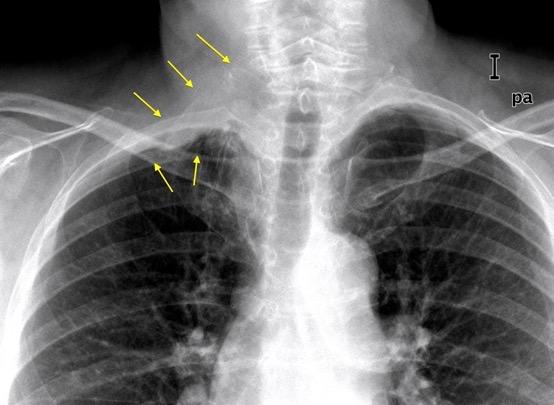

Hernia pleural con derrame en la pared abdominal y fracturas costales

Ioannidis O et al. Transdiaphragmatic Intercostal Hernia. An Unusual Hepatic Injury After a Car Accident: A Case Report and Review of the Literature . Discoveries 2021, /IDetorakis EE et al. Intercostal lung herniation - The role of imaging . Radiology Case. 2014